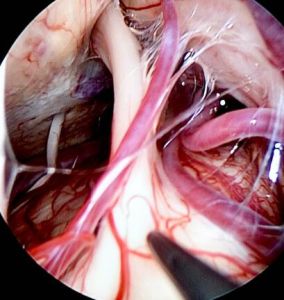

3、微血管減壓術(micorvascular decompression, MVD)

MVD手術是目前原發性三叉神經痛首選的手術治療方法。1967年由Jannetta教授首次提出,手術適應症包括:經影像學檢查確認三叉神經為血管壓迫者;其它治療效果差願意接受手術者;壓迫三叉神經產生疼痛的血管稱之為“責任血管”。

常見的責任血管有:

①小腦上動脈(75%),小腦上動脈可形成一向尾側延伸的血管襻,與三叉神經入腦幹處接觸,主要壓迫神經根的上方或上內方。

②小腦前下動脈(10%),一般小腦前下動脈從下方壓迫三叉神經,也可與小腦上動脈一起對三叉神經形成夾持壓迫。

③基底動脈,隨年齡增長及血流動力學的影響,基底動脈可向兩側彎曲而壓迫三叉神經根,一般多彎向較細小的椎動脈一側。

④其它少見的責任血管還有小腦後下動脈、變異血管(如永存性三叉動脈)、腦橋橫靜脈、外側靜脈及基底靜脈叢等。責任血管可以是一支也可以是多支,既可以是動脈也可以是靜脈。

微血管減壓術的方法是:全麻下,於患側耳後、髮際內縱行4cm的直切口,顱骨開孔,直徑約2cm,於顯微鏡下進入橋小腦角區,對三叉神經走行區進行探查,將所有可能產生壓迫的血管、蛛網膜條索都“鬆懈”開,並將這些血管以Tefflon墊片與神經根隔離,一旦責任血管被隔離,產生刺激的根源就消失了,三叉神經核的高興奮性就會隨之消失,恢復正常。絕大多數患者術後疼痛立即消失,並保留正常的面部感覺和功能,不影響生活質量。